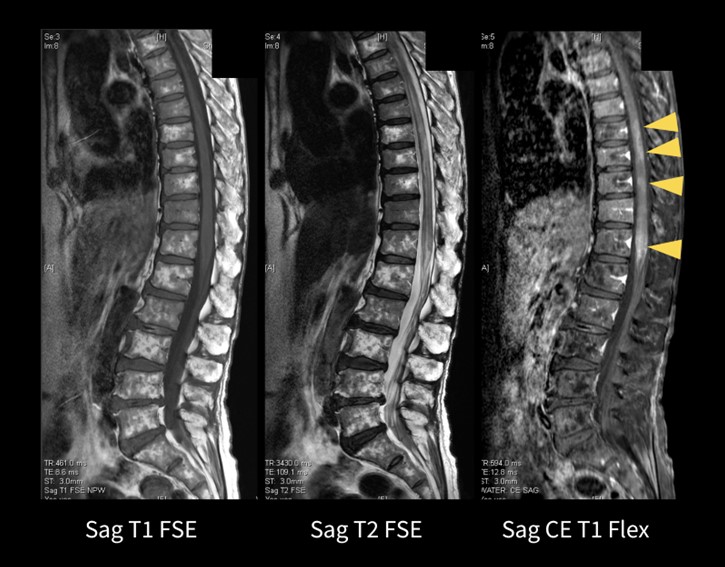

Flexible No Phase Wrap

従来は、No Phase Wrap(以下、NPW)の値を直接設定することが出来ず、オーバーサンプリングが必要な撮像において、必要以上に撮像時間の延長が生じる場合があった。アップグレード後はNPWの値を直接入力でき、位置決め画像上でオーバーサンプリング領域が表示されるため、被写体に対してより柔軟にオーバーサンプリングと撮像時間の最適化を行うことが可能になった。

本症例は、脱髄性疾患や脊髄炎疑いの患者さんの造影検査である(図.8)。撮像範囲の指示は胸椎5番から腰椎5番までと広範囲であったが、位相FOV(位相方向=SI)を広げることで空間分解能は維持しつつ、NPWの値を調整することで、結果的には撮像時間の延長なく画像取得できた。撮像範囲が広く脂肪抑制不良が懸念されるため、造影後はFlexを用いて撮像した。従来IDEALを用いて4分程度で撮像していたが、Flexでは3分程度で均一な脂肪抑制画像を得ることができた。胸髄を中心とした病変部も明瞭に描出されている。

図8.FLEXを用いた脊椎造影検査